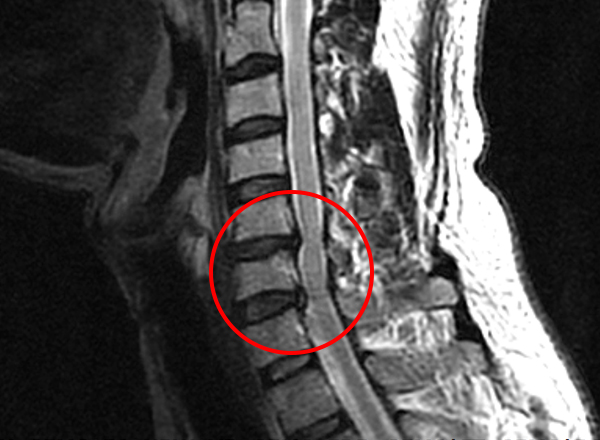

목디스크란 목뼈 사이에 있는 디스크가 손상되어 신경을 압박하는 질환을 의미합니다. 디스크는 젤리와 같은 수핵과 섬유륜으로 구성되어 있습니다. 섬유륜이 손상되면 수핵이 밖으로 밀려나와 신경을 압박하게 됩니다.